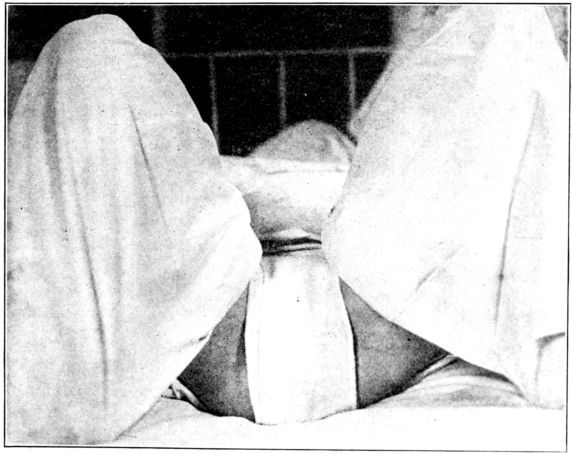

| 183. | Obtaining a 24–hour specimen of urine from the baby | 527 |

| xxiv184. | Band to hold baby’s legs while obtaining specimens of urine | 527 |

| 185. | Belt used to hold tube for specimen | 528 |